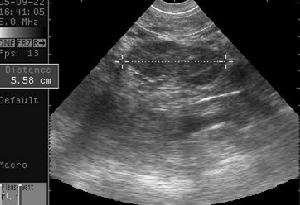

濾泡囊腫和黃體囊腫均與月經周期關係密切,前者為排卵前的卵巢囊性增大,若發生破裂時,一般不伴陰道流血;後者則為月經前的卵巢囊性增大,當破裂時,除急腹症症狀外,常伴陰道流血。二者之破裂與異位妊娠之破裂鑑別困難,常需根據剖腹探查發現及病理學檢查始能作出最後診斷。 臨床用子宮造影、宮腔鏡檢查、可為診斷黃體囊腫提供有力證據,但這些檢查複雜且有創傷,患者難以接受,而B超檢查簡單易行、直觀準確,對患者無痛苦、無損傷,從而使患者樂於接受。患者宮頸管囊腫,圖像清晰,對於宮頸管小到3~4mm的病灶也能檢出,且聲像圖特徵性強、診斷明確。與其它疾病易於鑑別。上述兩種囊腫破裂需手術時,單純切除囊腫並修復卵巢即可。

(2)B超患側卵巢增大,腹腔積液。